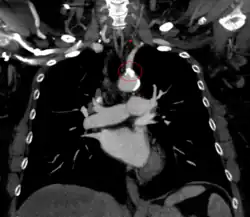

Diagnosis

The evaluation for this condition includes: